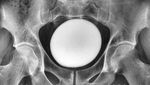

Dokter di Iran menemukan sebuah batu kandung kemih seperti telur raksasa. Diameternya 11 cm dengan berat 826 gram. (Foto: Nephro-Urology Monthly)

Setelah operasi, dokter memasang kateter untuk membantu proses pengeluaran urine dari kandung kemih selama masa pemulihan. Kateter tersebut dilepas tujuh hari setelah tindakan bedah dilakukan. (Foto: Nephro-Urology Monthly)